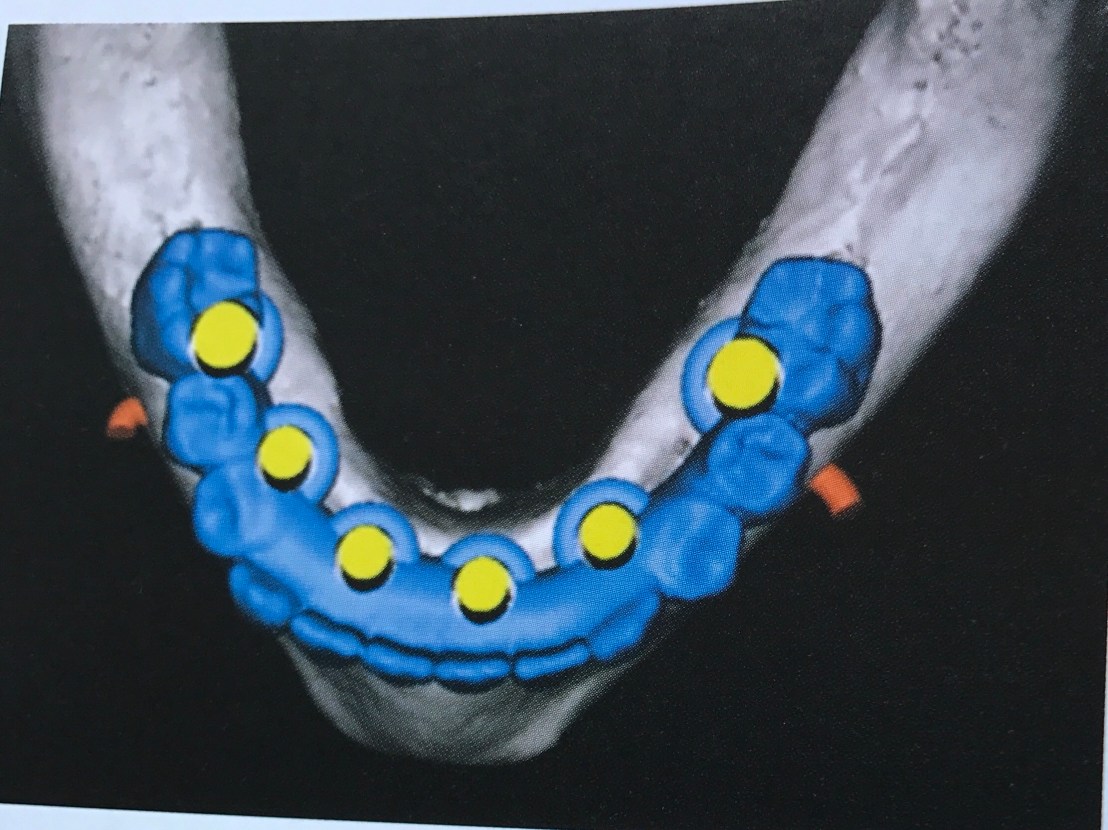

แสดง Ideal Implant placement สำหรับ Removable Prosthesis (Occlusal view)

แสดงปริมาณ Bone ที่เราต้องคำนึงใน 3 มิติ ที่นอกจากจะมีผลต่อ diameter และความยาวของ Implant แล้ว ยังต้องคำนึงถึง angulation ของแรงที่ทำต่อ Implant ด้วย